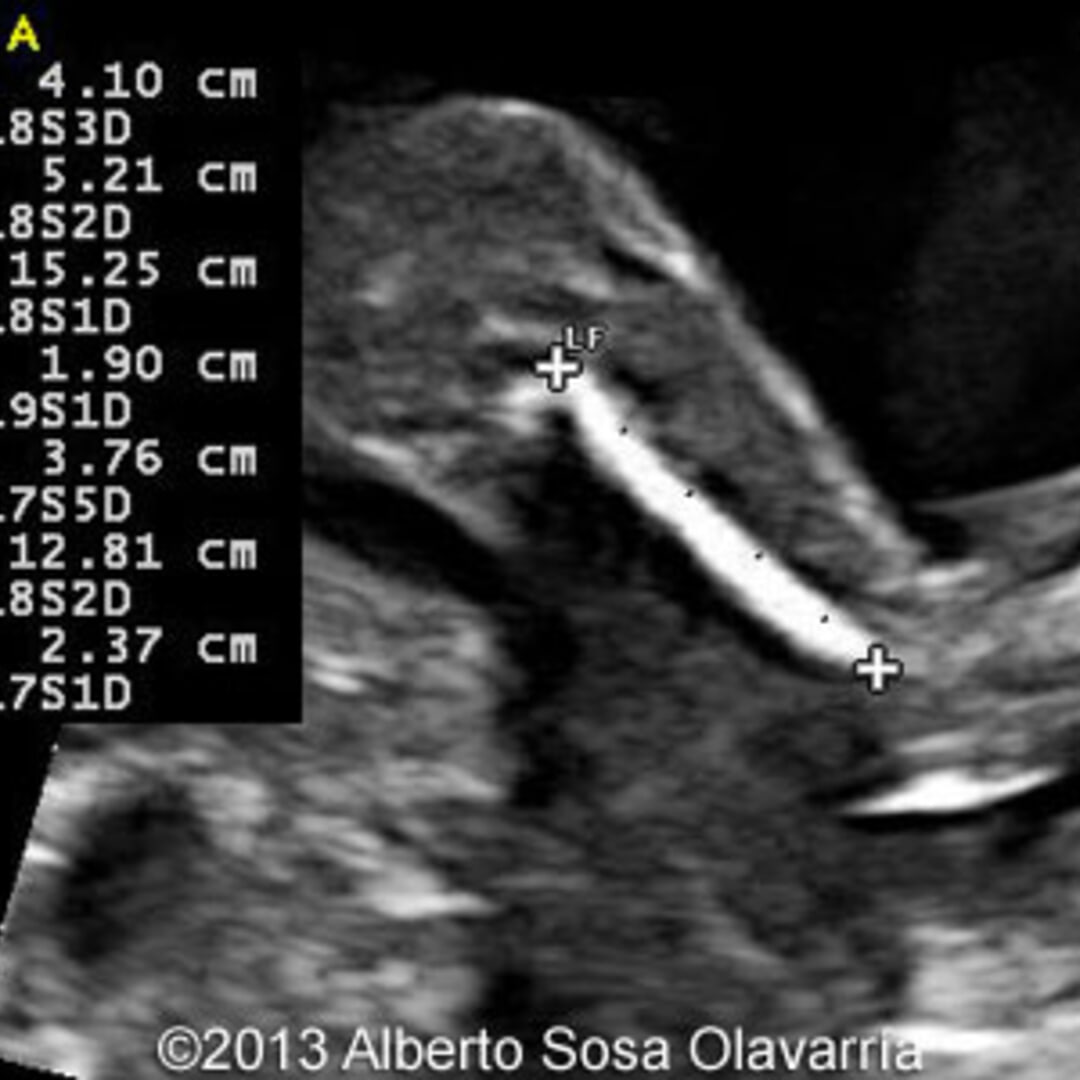

Molar Pregnancy Information. Ultrasound Included. - Ultrasoundfeminsider

Molar pregnancy information. Ultrasound included. - Ultrasoundfeminsider ultrasoundfeminsider.com

ultrasound pregnancy molar weeks baby information included testing